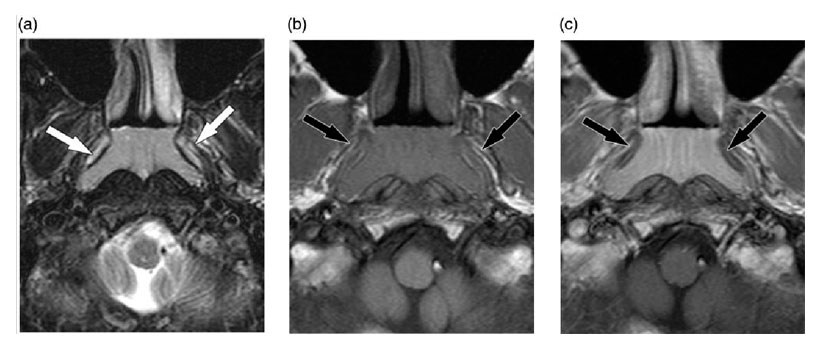

En las imágenes T1-w, la mayoría de las lesiones (95,4%) fueron hipointensas en comparación con la musculatura adyacente. En las imágenes saturadas de grasa T2-w, el 82,4% de las lesiones eran hiperintensas. Después de la administración intravenosa de medio de contraste, la mayoría de las lesiones mostraron una ligera mejoría (58,6%). Se observó una mejora moderada en el 32,4% y se identificó una mejora marcada en el 9,0%. En el grupo de 0 a 9 años de edad, la mayoría de las lesiones mostraron una leve mejoría. Se identificaron quistes dentro de la HA en 433 casos (35.9%). La frecuencia de los quistes aumentó continuamente con la edad, es decir, del 10,9% al 65,2%.